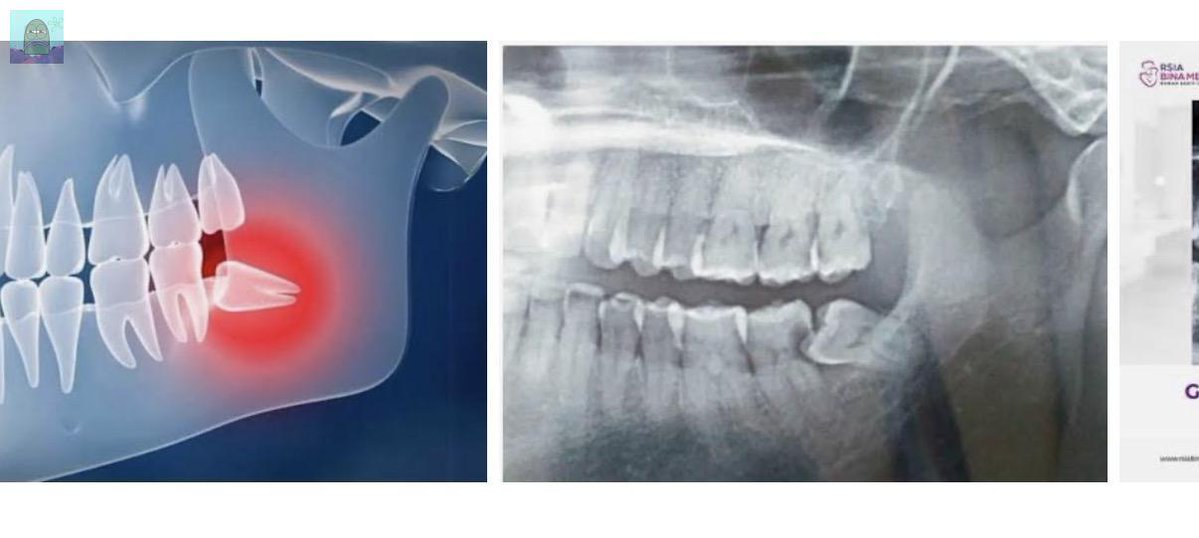

💚 guys mau tanya dong, gigi bungsu tuh kalo ga ngerasain sakit gapapa kah ga dicabut? atau harus dicabut ya? soalnya gigi bungsuku tuh tumbunya miring gitu, trs semisal kalo ga dicabut ada efeknya ga buat kedepannya?

rahangku bawahnya agak miring, mirip gini & ga bisa mangap lebar. Diobati kemana ya? Ada rekomendasi klinik/tempat pijet benerin gini dmn&budget brp? Tanyarl